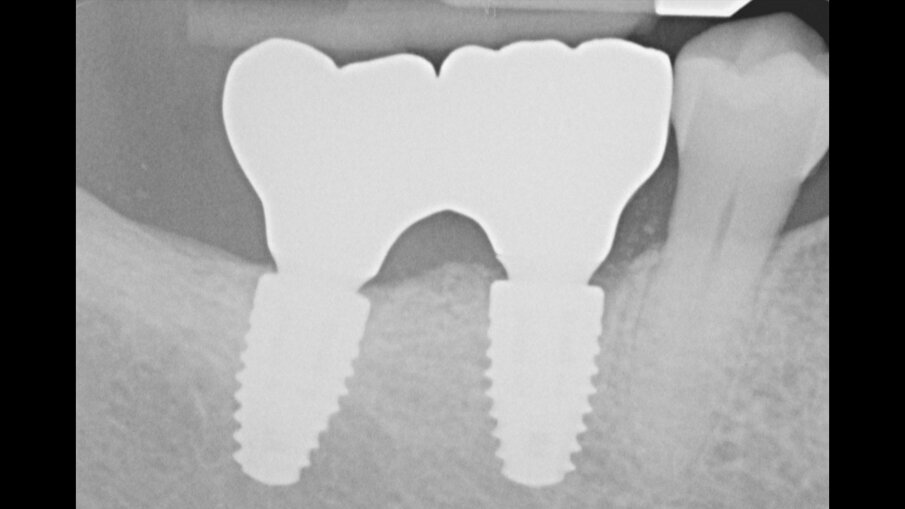

Figg. 19a, 19b_Immagine clinica e radiografica che mostrano il manufatto protesico finale.

Figg. 20a, 20b_Controllo clinico e radiografico a due anni dal carico protesico.